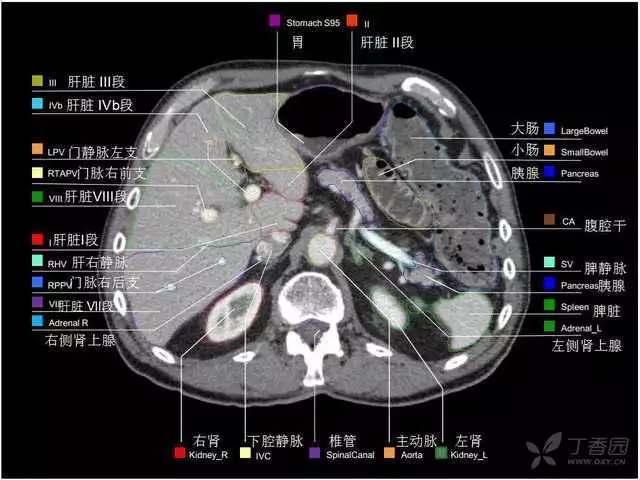

腹部肝脏高清CT断层的图谱

全腹部高清CT图谱,淋巴结彩色图谱,血管解剖图谱大汇总!